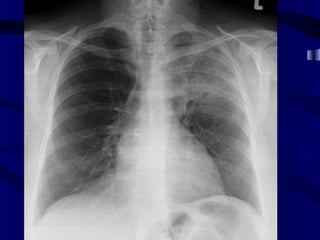

Paratracheal ln

Right Paratracheal Lymphadenopathy